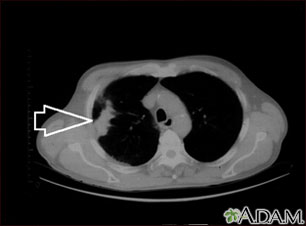

TC de la parte superior del tórax que muestra una masa en el pulmón derecho (se puede observar al lado izquierdo de la imagen).